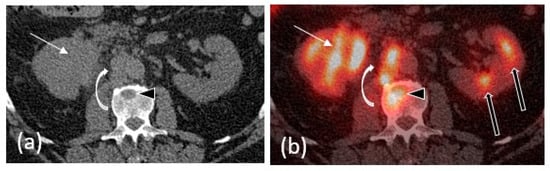

2.5. PET/CT

- Tanaka, H.; Yoshida, S.; Komai, Y.; Sakai, Y.; Urakami, S.; Yuasa, T.; Yamamoto, S.; Masuda, H.; Koizumi, M.; Kohno, A.; et al. Clinical value of 18F-fluorodeoxyglucose positron emission tomography/computed tomography in upper tract urothelial carcinoma: Impact on detection of metastases and patient management. Urol. Int. 2015, 96, 65–72. [Google Scholar] [CrossRef] [PubMed]

- Voskuilen, C.S.; Schweitzer, D.; Jensen, J.B.; Nielsen, A.M.; Joniau, S.; Muilwijk, T.; Necchi, A.; Azizi, M.; Spiess, P.E.; Briganti, A.; et al. Diagnostic value of 18F-fluorodeoxyglucose positron emission tomography with computed tomography for lymph node staging in patients with upper tract urothelial carcinoma. Eur. Urol. Oncol. 2020, 3, 73–79. [Google Scholar] [CrossRef] [PubMed]

- Zattoni, F.; Incerti, E.; Moro, F.D.; Moschini, M.; Castellucci, P.; Panareo, S.; Picchio, M.; Fallanca, F.; Briganti, A.; Gallina, A.; et al. 18F-FDG PET/CT and urothelial carcinoma: Impact on management and prognosis—A multicenter retrospective study. Cancers 2019, 11, 700. [Google Scholar] [CrossRef] [PubMed]